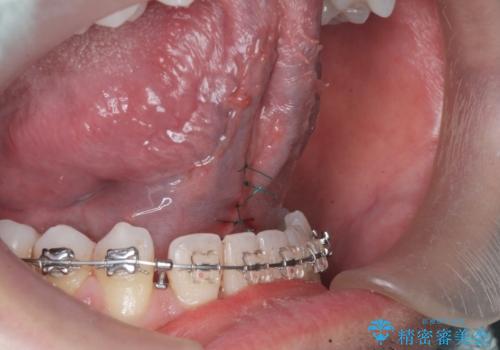

舌小帯の切除

抜糸は1週間から2週間の期間を置いた後治癒を確認してから行います。

- 外科手術のため、術後に出血、痛みや腫れ、違和感を伴います